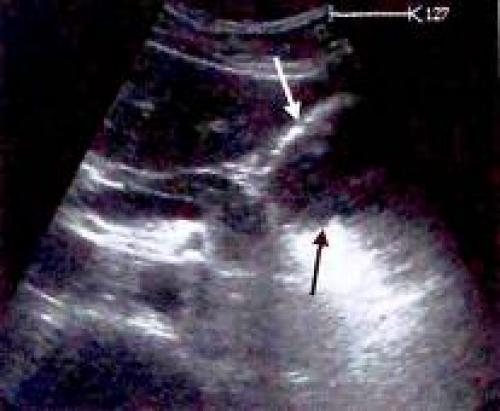

Визуализация тела желудка на продольном сечении

У неподготовленного к обследованию пациента тело желудка визуализируется только как постоянно изменяющееся поле позади левой доли печени. При имеющемся исходном изображении гастроэзофагеального перехода найти эту область достаточно просто.

Рис. 6. Визуализация тела желудка на продольном сечении:

продольное сечение через печень и гастроэзофагеальный переход (^);

Рис. 7. Визуализация тела желудка на продольном сечении:

датчик смещен влево. Срез желудка расширился (v);

Рис. 8. Визуализация тела желудка на продольном сечении: латеральное продольное сечение. Видна полость желудка, заполненная твердыми частицами и газом (v

В случае если ультразвуковой сигнал попадает на стенку желудка по касательной, проходя при этом через многочисленные складки слизистой оболочки, может сформироваться ошибочная картина утолщения стенки желудка (см. рис. 5). С другой стороны, массивный отек стенки желудка может быть не диагностирован даже при наличии у пациента клинических проявлений (анорексия, снижение массы тела, вздутие живота, отвращение к жареной пище), в случае если не удается осуществить визуализацию всех отделов желудка. Для оценки тела желудка исследование выполняется в левой косой подреберной плоскости, для оценки кардиального отдела и входа в желудок - в высокой продольной околосрединной плоскости выше аортального отверстия диафрагмы.

Рис. 9. Многочисленные складки слизистой оболочки могут имитировать утолщение стенки желудка, в случае если они располагаются по касательной к ультразвуковому сигналу.